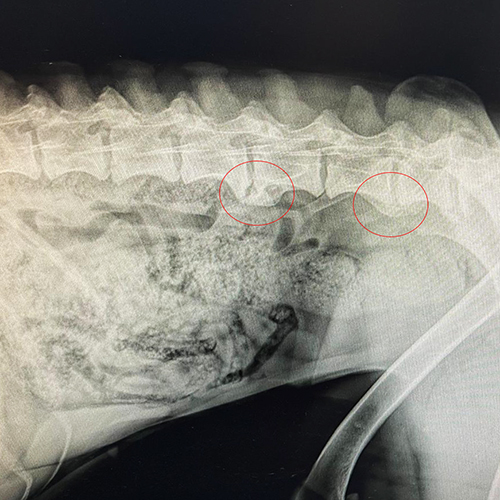

Die Diagnose erfolgt in der Regel über Röntgenaufnahmen. Spondylose wird dabei häufig als Zufallsbefund entdeckt. Es ist wichtig, andere Erkrankungen wie Bandscheibenvorfälle oder Arthrosen der Wirbelgelenke abzugrenzen.

Bei einer Spondylose bilden sich an den Rändern der Wirbelkörper knöcherne Auswüchse – sogenannte Spondylophyten. Sie entstehen, weil der Körper versucht, die Wirbelsäule zu stabilisieren und die Bandscheiben zu entlasten. Im Laufe der Zeit können diese Knochenzubildungen ganze Wirbelsegmente miteinander verbinden. Das macht die Wirbelsäule weniger beweglich und kann z.T zu massive Schmerzen führen und in schweren Fällen können die knöchernen Veränderungen neurologische Probleme verursachen.